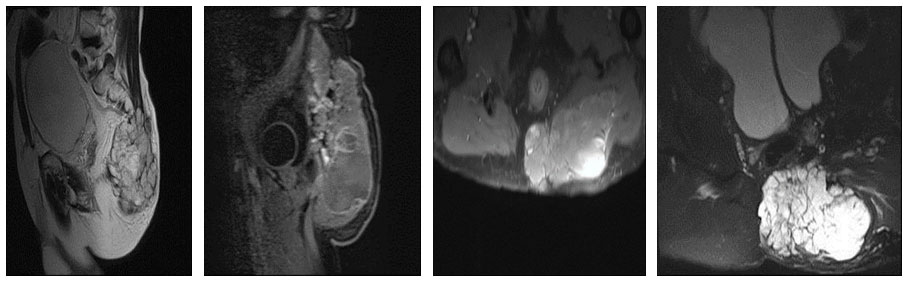

Ameliyat öncesi: MR’da aynı bölgede kas içine uzanan ve rektuma bası yapan büyük ve düzensiz tümör dokusu görülmekte